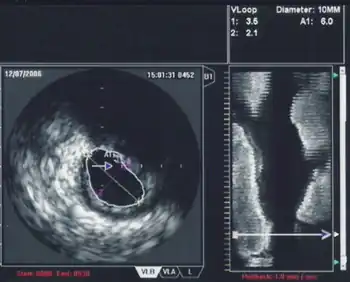

Intravascular ultrasound (IVUS) or intravascular echocardiography is a medical imaging methodology using a specially designed catheter with a miniaturized ultrasound probe attached to the distal end of the catheter. The proximal end of the catheter is attached to computerized ultrasound equipment. It allows the application of ultrasound technology, such as piezoelectric transducer or CMUT, to see from inside blood vessels out through the surrounding blood column, visualizing the endothelium (inner wall) of blood vessels.[1]

The ultrasound catheter tip is slid in over the guidewire and positioned, using angiography techniques so that the tip is at the farthest away position to be imaged. The sound waves are emitted from the catheter tip, are usually in the 20-40 MHz range, and the catheter also receives and conducts the return echo information out to the external computerized ultrasound equipment which constructs and displays a real time ultrasound image of a thin section of the blood vessel currently surrounding the catheter tip, usually displayed at 30 frames/second image.

The (a) blood vessel wall inner lining, (b) atheromatous disease within the wall and (c) connective tissues covering the outer surface of the blood vessel are echogenic, i.e. they return echoes making them visible on the ultrasound display.

By contrast, the blood itself and the healthy muscular tissue portion of the blood vessel wall is relatively echolucent, just black circular spaces, in the images.

Heavy calcium deposits in the blood vessel wall both heavily reflect sound, i.e. are very echogenic, but are also distinguishable by shadowing. Heavy calcification blocks sound transmission beyond and so, in the echo images, are seen as both very bright areas but with black shadows behind (from the vantage point of the catheter tip emitting the ultrasound waves).

When using IVUS to determine whether an individual's left main disease is clinically significant, in terms of the desirability of physical intervention, the two most widely used parameters are the degree of stenosis and the minimal lumen area.[12] A cross sectional area of ≤7 mm² in a symptomatic individual or ≤6 mm² in an asymptomatic individual[13] is considered to be clinically significant and warrants intervention to improve one-year mortality. However, these exact cutoffs are up for debate and different cutoff cross-sectional areas may be used in practice depending on differing interpretations of the trial data.